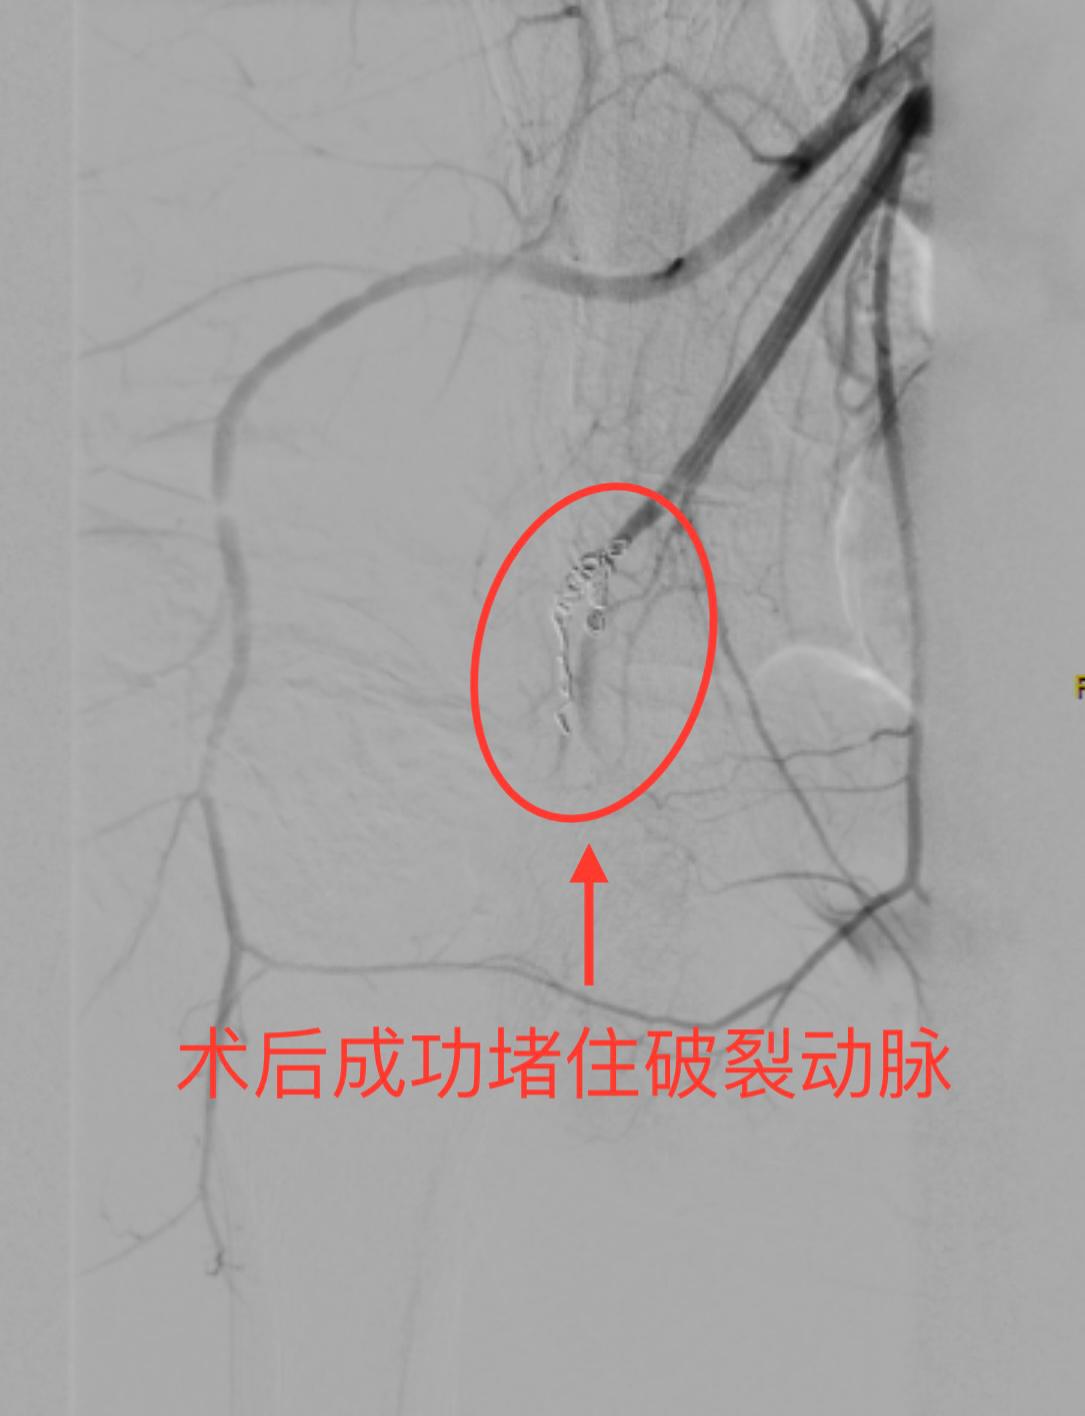

血管外科主任李良学接到通知后,第一时间奔赴导管室,决定采用经皮DSA经导管髂内动脉栓塞术精准堵住出血点。导管室内,在DSA的引导下,李良学双手稳稳地操作着导管穿过错综复杂的血管,准确抵达出血点,将弹簧圈顺利置入,成功堵住了破裂的动脉。

破裂出血的动脉被成功堵住。